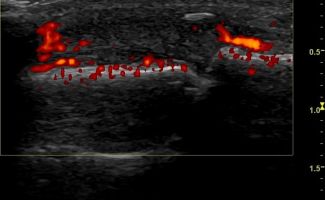

Rheumatic Diseases

- Rheumatoid Arthritis

- Psoriatic Arthritis